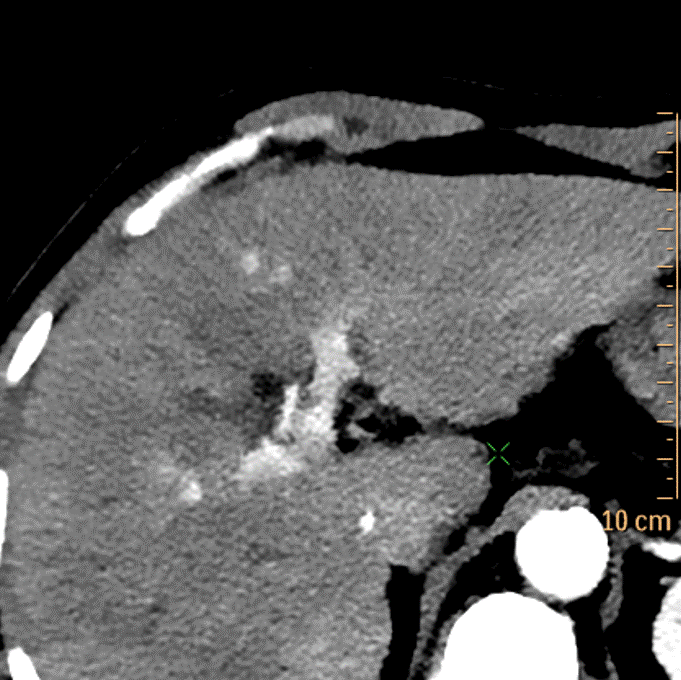

Arterial phase, conventional image. Scan done with 35 mL contrast. See the enhancement?

Arterial phase, 40 keV mono-E image. No comment needed.